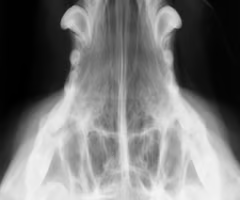

Which side is abnormal?

R - Mineralization and fluid in canal/ bulla